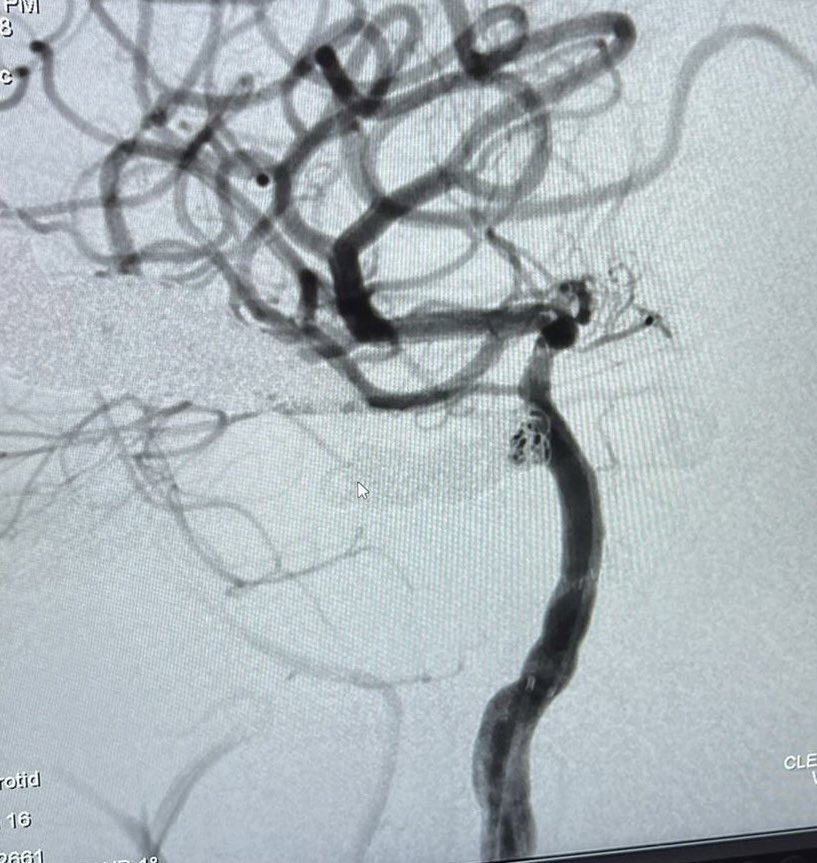

We successfully inserted endovascular coils in a pt with carotid cavernous fistula at Muhimbili Orthopaedic Institute(MOI) with the NeuroIntervention teams led by Drs. Faheem Sheriff Karol Budohoski as we bridge our way to establishing capacity for neurovascular interventions in Tanzania!

We successfully inserted endovascular coils in a pt with carotid cavernous fistula at <a href="/MuhimbiliOrtho1/">Muhimbili Orthopaedic Institute(MOI)</a> with the NeuroIntervention teams led by Drs. <a href="/faheem_sheriff/">Faheem Sheriff</a> <a href="/karolbudohoski/">Karol Budohoski</a>

as we bridge our way to establishing capacity for neurovascular interventions in Tanzania!